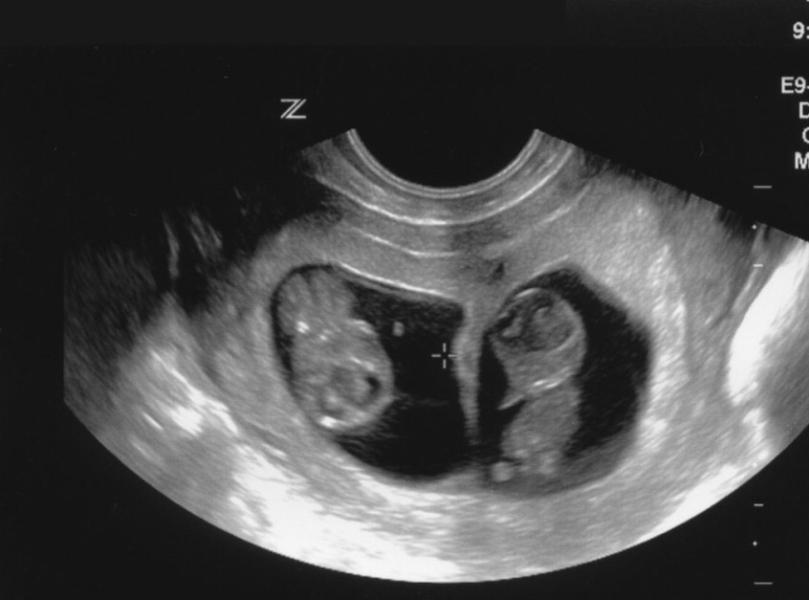

Но когда я увидела это фото, меня будто током шибануло...

Эти два маленьких человечка, которым 12 недель и я смотрю на них и улыбаюсь.🥲

А после ... размышления... не, я конечно молодая и бодрая. И я буду им безумно рада. 💯% . Особенно от того что их там двое.

Я даже не знаю, мальчики там или девочки. А может и мальчик и девочка🥰 Это такой подарок 🎁

Сразу два малыша👶🏼👶🏼... разумеется это может произойти с каждым человеком, и пусть у тех кто мечтает о таком чуде, оно обязательно исполнится. 🤰🏻👍🏼 а на самом деле я не знаю кто их родители, но очень рада за них🥳